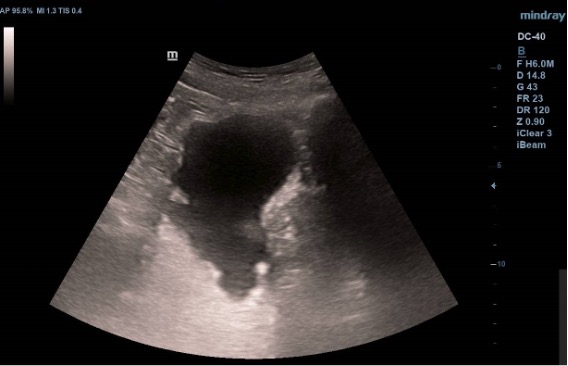

Ecografía vesical: Pared irregular, múltiples lesiones polipoides, la mayor (2.07 cm) en pared posteroinferior. Una lesión polipoiea dependiente de la próstata de 1,6 cm. Otra lesión más craneal en pared posterior de 1.26 cm, y cerca de uréter derecho una de 2 cm.  Además, varias lesiones polipoides más pequeñas en cara anterior y lateral derecha.